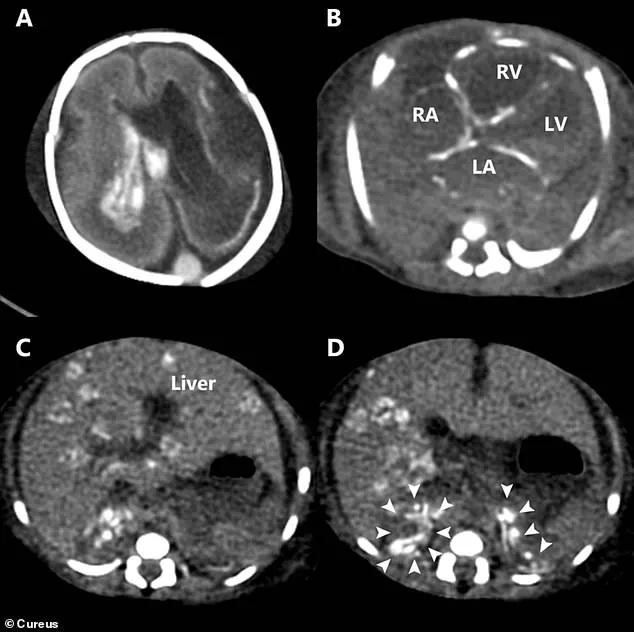

Post-mortem imaging, including a CT scan, revealed the full extent of the infection's damage: widespread calcium deposits in the heart, liver, and adrenal glands, signs of chronic inflammation; bleeding within the brain's ventricles; and extensive tissue destruction across multiple organs.

The post-mortem examination confirmed the presence of HSV-2 through tests on the baby's skin and blood samples, revealing that the mother, though asymptomatic, had carried the virus in her body for years.